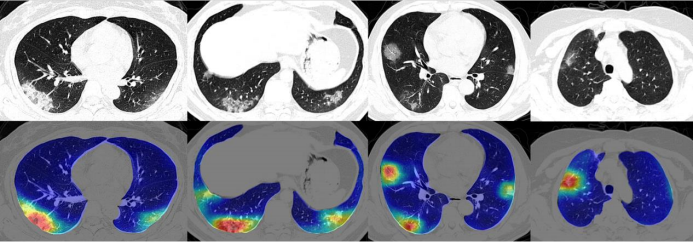

In yet another paper, titled Rapid AI Development Cycle for the Coronavirus (COVID-19) Pandemic: Initial Results for Automated Detection & Patient Monitoring using Deep Learning CT Image Analysis, the authors use a 3-D U-Net architecture to extract the lung out of the scan (same function as the VNET20 model).

Then these lung crops are classified by a neural network. The entire lung is passed to the classification network, unlike the previous work where ROIs were extracted from the lung before classification. The authors then use the Grad-CAM technique to create "heatmaps" of the lungs.

To classify each patient, multiple slices of the CT scan are used. Each of these scans are used to compute the class probabilities. The patient is classified as COVID-19 positive if a majority of the slices have COVID-19 as the highest class probability. (In other words, each slice counts as a vote).

In addition to classifying 2-D lung crops, the authors also use an off-the-shelf software, RADLogics, that detects nodules and small opacities within a 3-D lung volume. Then, the patches from the software and the heatmaps from the earlier stages are combined to create a 3-D visualization.

The volume of patches is then used to create a "Corona Score".